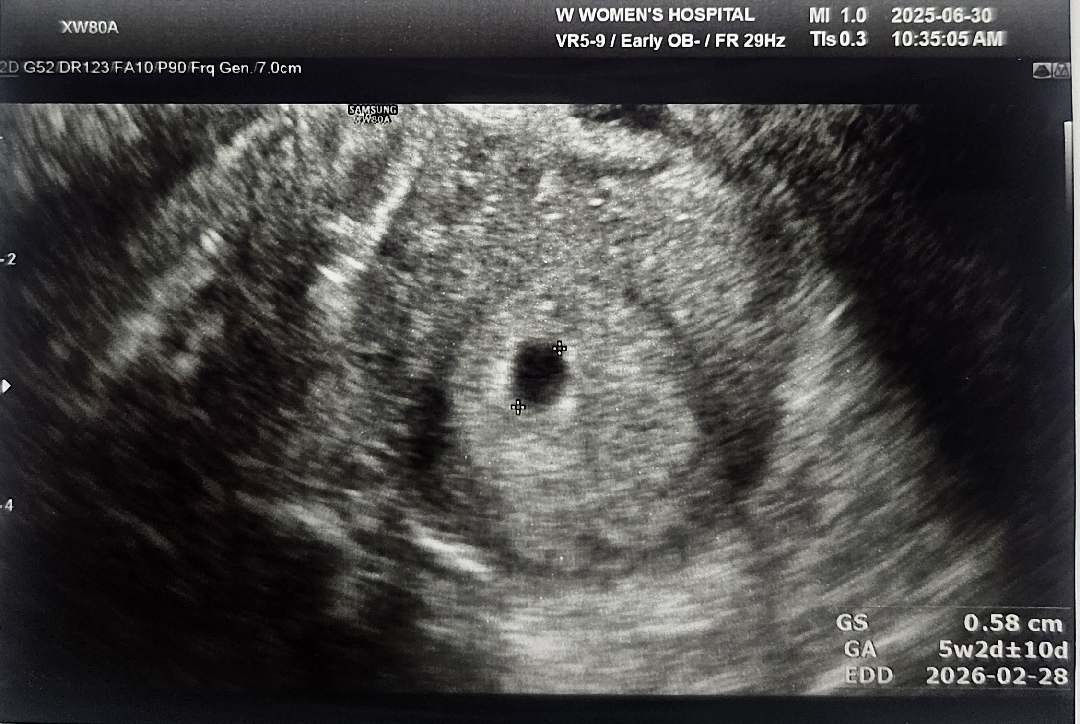

오늘 처음으로 아기집 보고 왔어요! 원래 계산대로라면 5주 4일인데요 원장님께서 초음파로 아기집 보시고는 그냥 5주쯤 되었다고만 말씀하시더라구요!! 다른 분들 말씀들어보면 구체적으로 이것저것 듣고 오시는 것 같은데..ㅠㅠ 저는 그냥 임신 확인증만 주시고 2주후에는 아기까지 볼 수 있으니 그때 오라는 말씀만 하시네용🥹 뭐 난황이라던가 아기집 위치라던가 피고임 등등 문제가 있었다면 원장님께서 먼저 말씀해주셨겠죵? 별 문제 없냐고 여쭤보니 지금은 뭐 문제 생길게 없다는 말씀만 하셔서요ㅎㅎ 저희 할머니부터 뵌 원장님이라 실력은 확실하신데도 불구하고 제가 넘 예민보스 걱정인형인건지ㅠㅠㅠ 의견 나눠주시면 감사하겠습니다!